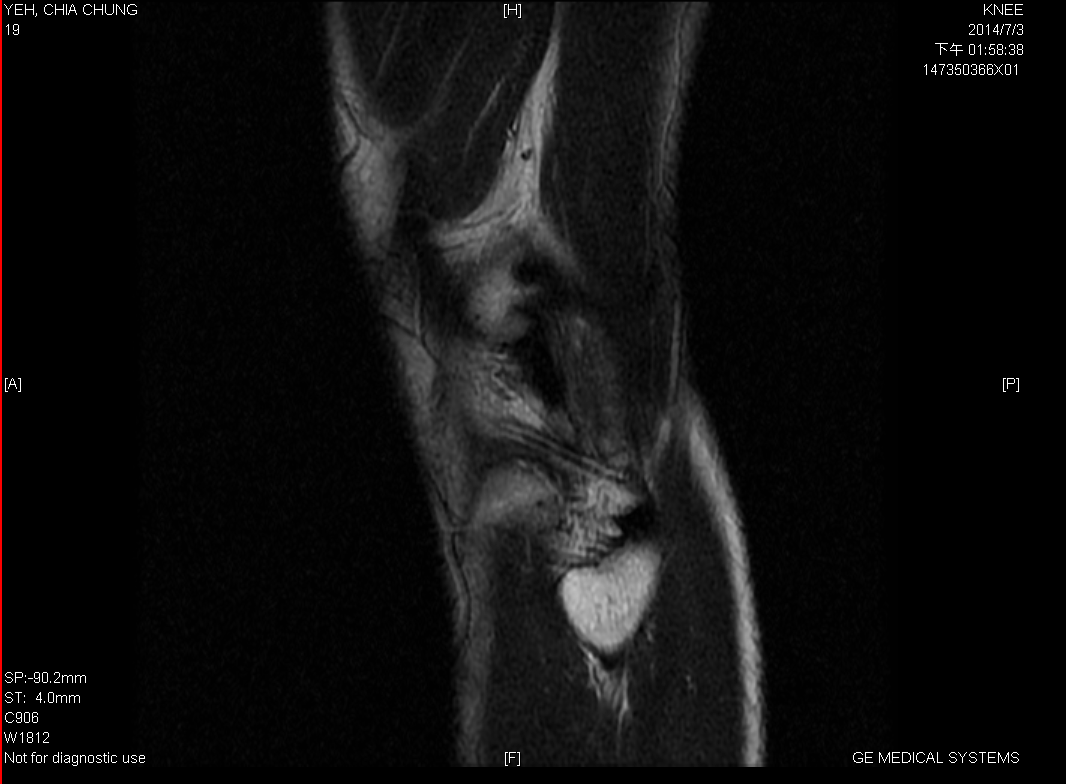

3_MR_LT, Sag T2

4_MR_LT, Sag PD